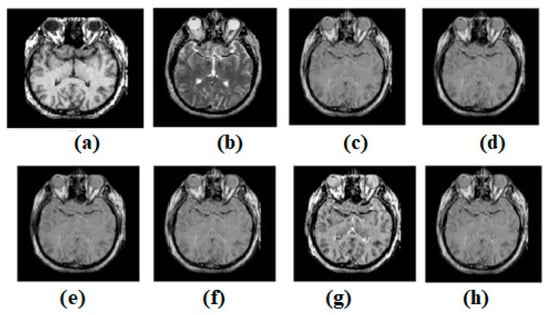

Figure 5.

(a) Source image: MR-T2, (b) Source Image: SPECT, (c) Result of [44], (d) Result of [47], (e) Result of [48], (f) Result of [49], (g) Result of [51], (h) Result of [53].

As shown in Figure 5, on the MR-T1 image and the MR-T2 image, the latest methods were also checked. Figure 5a,b shows the corresponding MR-T1 and MR-T2 images. Figure 5c–g shows the results of [44,47,49,51,53], respectively. It is evaluated from visual inspection that the approaches to visual consistency described in [53] are stronger in terms of edges and content definitions compared to the existing methods. The overall visual quality of [51,53] is comparatively better. However, [53] outperforms [51]. Refs. [44,47] also show better texture preservation; in some cases, however, artifacts are observed. Ref. [49] shows great results in terms of edge preservation and smoothness in uniform and non-uniform areas. As shown in Figure 5, ref. [44] preserves edges and textures poorly. However, differences exist. The original texture is preserved in various places. In a diverse domain, clarity is lacking. Ref. [47]’s output is adequate, but it fails to preserve the edges and texture, as shown in Figure 5. However, contrasts are maintained well. The texture is consistent in certain spots. However, the diverse zone lacks light. Ref. [49] in Figure 5 preserves edges and textures poorly. The contrasts in ref. [48] were wonderfully preserved. Some portions are consistent, and the original texture has been carefully maintained. These places are not the only ones with texture changes. In heterogeneity, light levels are inadequate. In Figure 5, ref. [51]’s result is good, but it fails to preserve the image’s edges and textures. However, contrasts have been maintained. Several areas of continuity and texture preservation have been achieved. The heterogeneous zone has inconsistent brightness. Figure 5 shows ref. [53]’s passable output, but it loses edges and textures. Nevertheless, the distinctions are well-maintained. The surface’s homogeneity and texture have been preserved in some areas. However, the non-uniform zone has poor brightness.